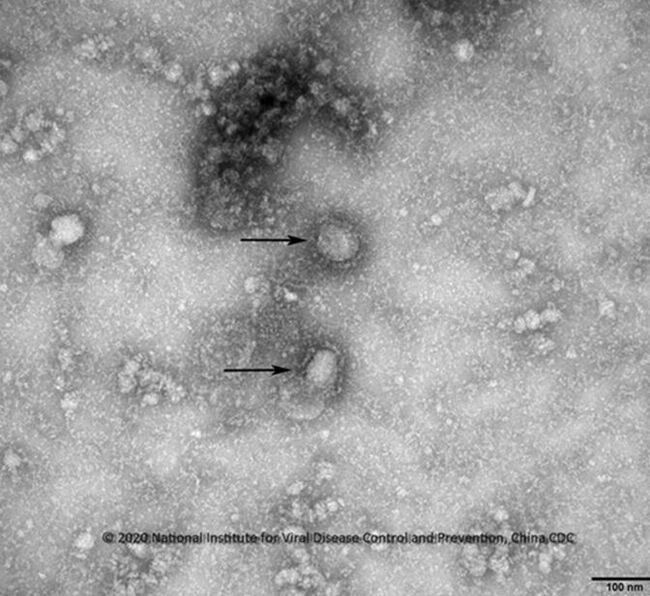

일부 환자는 문제의 우한시 전통시장 방문 이력이나 확진환자 또는 야생동물과 접촉한 적 없는데도 신종 코로나바이러스감염증을 앓는 점에서 사람 간 전파 가능성을 배제할 수 없다는 지적이 나온다.